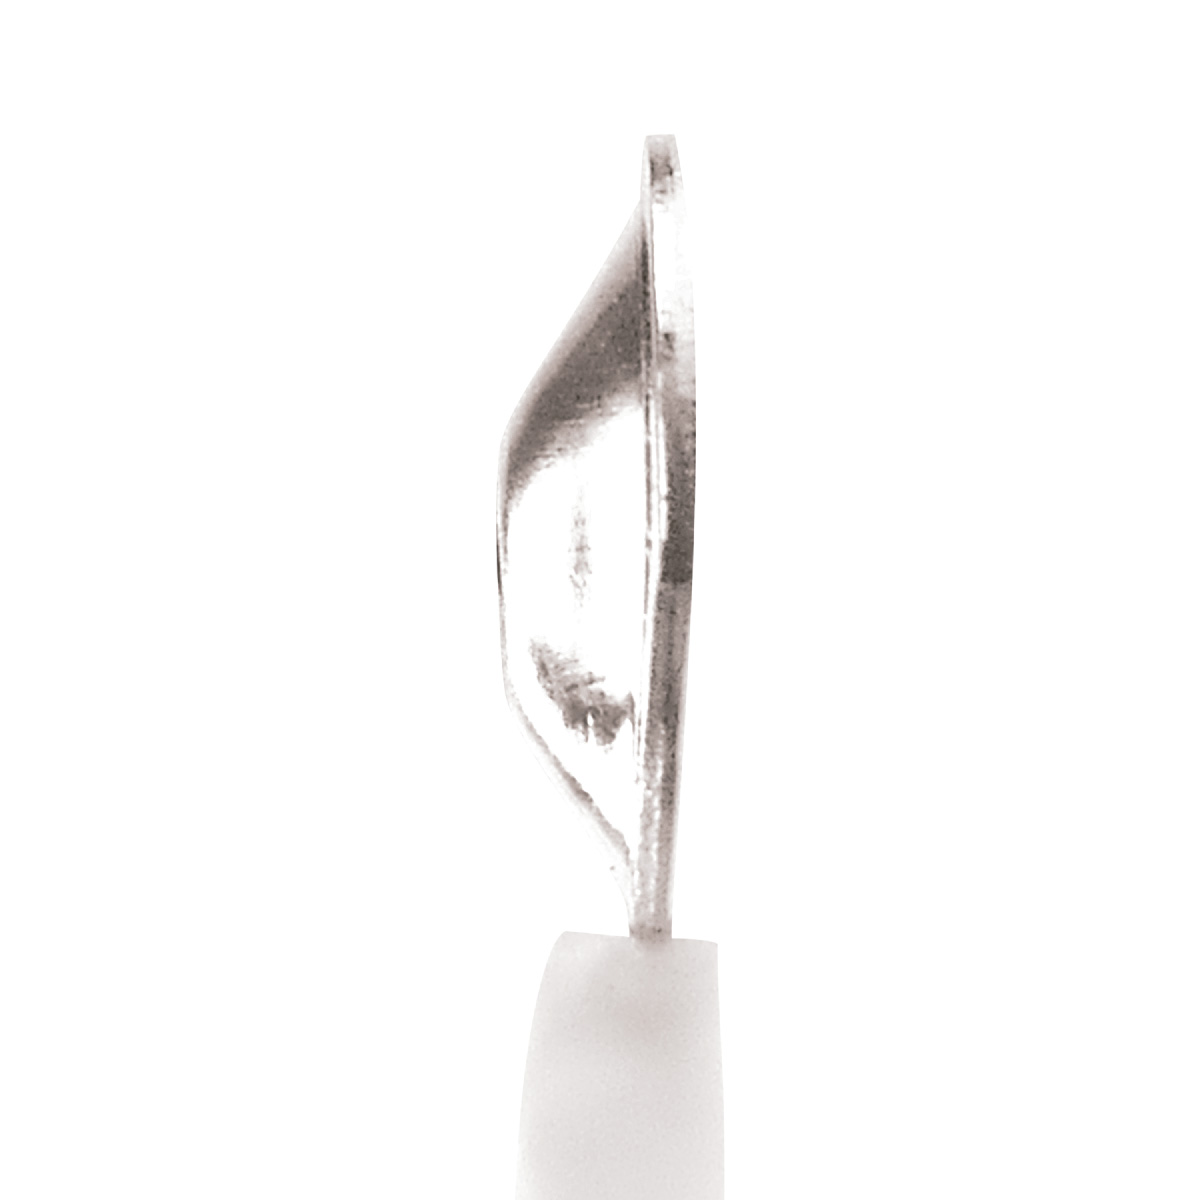

Os Eletrodos Concha de Prata são a escolha profissional para exames de EEG e PSG, combinando alta qualidade técnica e segurança. Fabricados com conector Touch Proof (pino de segurança), concha banhada a ouro e fios de Kevlar ultra-resistentes, garantem durabilidade excepcional e precisão na captação de sinais elétricos cerebrais.

– Concha banhada a prata para condutividade superior e redução de interferências.

– Conector Touch Proof: Elimina riscos de interferência e aumenta a segurança do paciente.